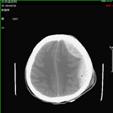

颅脑损伤——开展重型颅脑损伤的大骨瓣减压、后颅窝血肿清除减压、人工硬膜修补、矢状窦破裂修补、凹陷骨折整复、快速气管切开术;亚低温治疗,成功的挽救多名危重患者的生命。后期联合高压氧治疗、钙离子拮抗剂、促醒药物治疗、颅骨修补手术和康复治疗多种方法结合提高患者的生存率和生存质量。总结出重型颅脑损伤有效和规范的治疗方法。

1).硬膜外血肿 术前 术后

2).颅后窝血肿术前 术后

3).颅骨凹陷性骨折术前 术后

脑血管病——对于基底节区、各脑叶及小脑脑出血采用常规的开颅手术。尤其是及时清除血肿减压,打破脑出血后一系列恶性循环,降低患者的死亡率。开展大面积脑梗塞开颅去骨瓣减压颞肌贴附治疗成功抢救多名脑血管意外患者。同时开展脑室穿刺引流治疗脑室出血;脑积水脑室腹腔分流手术。

1).高血压脑出血 术前 术后

2).脑室出血 行脑室穿刺外引流 术前 术后

3).大面积脑梗死 术前 术后